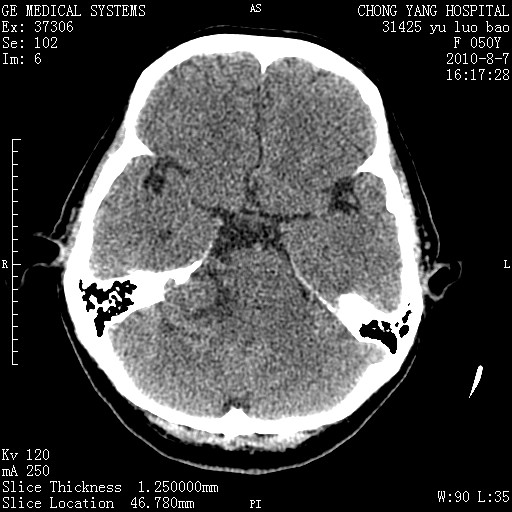

标题: CT28285:听力下降一年,头昏。 [打印本页]

标题: CT28285:听力下降一年,头昏。

右侧桥小脑角区占位--听神经瘤,建议增强或mri检查。

右侧桥小脑角去等密度占位,右侧内听道扩大、骨质吸收,考虑:右侧听神经瘤,建议增强检查。

右侧内听道扩大、骨质吸收,中脑受压左移,考虑:右侧听神经瘤,建议增强检查。支持!

骨窗示右侧内听道扩大,考虑右侧听神经瘤。

右侧桥小脑角区等密度占位,内耳道扩大,听神经瘤